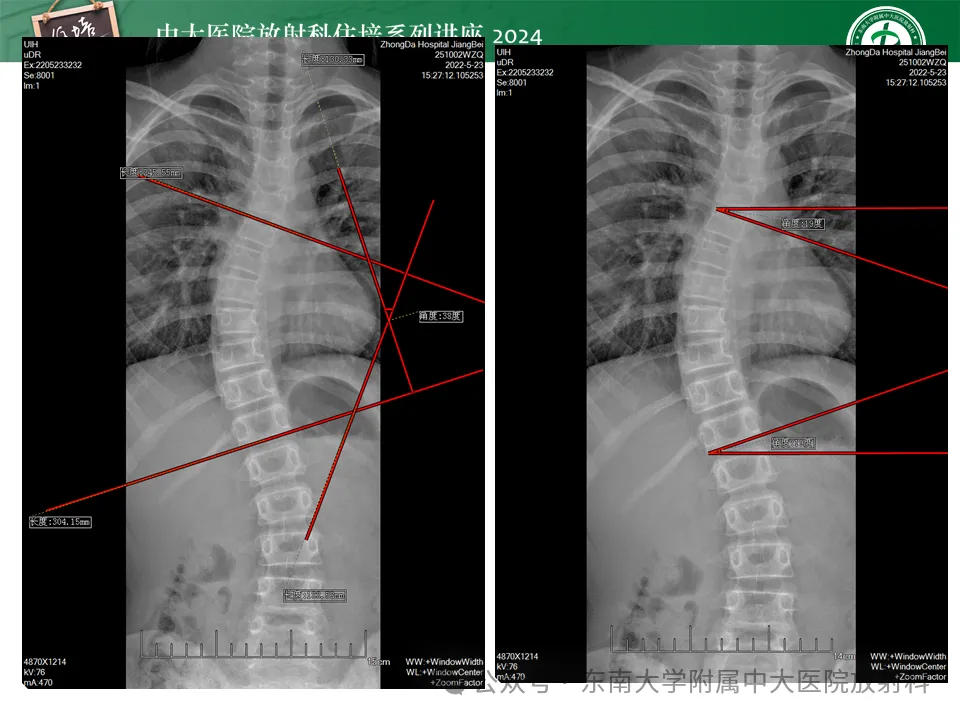

美式整脊具有一系列检查方式,进行脊椎物理检查,体态及关节活动分析,神经反射检测,以及全脊椎X光片,整体力学,功能分析,制定治疗方案。

董安立团队美式整脊培训着重理论和操作相结合方法进行教学,使学员掌握每一块脊椎矫正手法和方法,具有实用性、可操作性。学之能用,用之见效,可有效处理80%的常见问题。